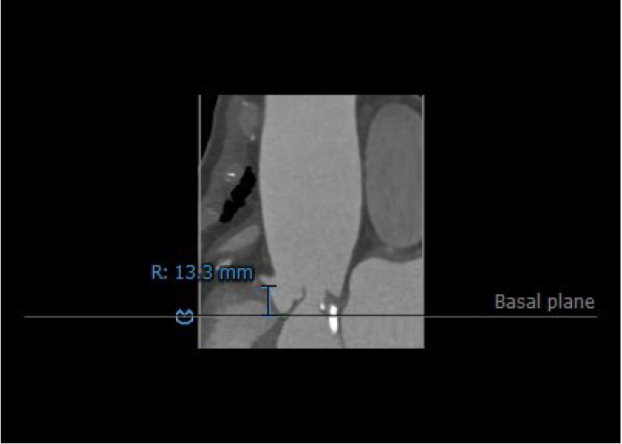

3.患者双侧冠脉开口高度尚可:LCA:10.4mm,RCA:13.3mm。

右冠开口高度:13.3mm